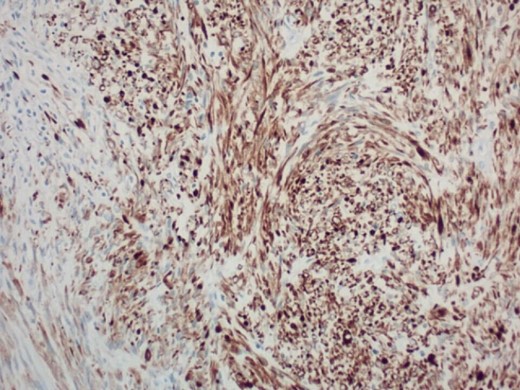

Pathology report was significant for mitotic figures on hematoxylin and eosin stain (Fig. 4). Immunohistochemistry showed actin positivity (Fig. 5) and desmin positivity (Fig. 6) in the tumor cells. All lymph nodes and margins were negative, with the smallest margin measuring 1.5 cm. The findings listed in the pathology report were consistent with primary leiomyosarcoma of the small bowel.

200× magnification of tumor cells. Immunohistochemical stain for smooth muscle actin is positive.